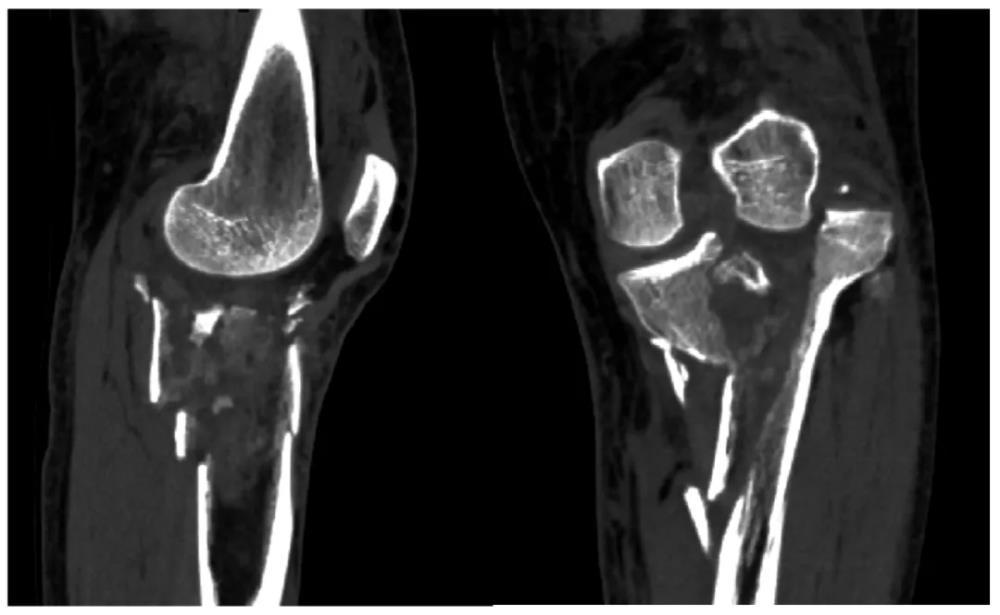

56岁的樊女士怎么也没想到,一次意外竟让她的左膝遭遇了如此严重的创伤。入院时影像检查结果触目惊心:左胫骨上段及胫骨平台粉碎性骨折,伴有股胫关节失稳。胫骨平台是膝关节重要的负重结构,粉碎性骨折后关节面平整度直接决定术后膝关节功能恢复情况,若复位不佳、固定不稳,极易引发创伤性关节炎、关节僵硬、行走疼痛、跛行等终身后遗症,严重影响中老年患者生活质量。

精准诊断:肉眼可见,左胫骨上段及胫骨平台呈粉碎性骨性结构中断,骨块分离情况严重;

关节评估:关节面粉碎骨折,关节面塌陷,外侧关节面向外上脱位,内侧关节面出现明显倾斜。

以前只能在电脑屏幕上通过二维或三维重建图像去想象,现在有了这个1:1的实体模型,就像是拿着‘破碎的瓷器’在拼图。通过实体模型,团队可以进行模拟手术,预演螺钉的进钉点、角度和长度,极大地提高了手术的精准度和安全性。